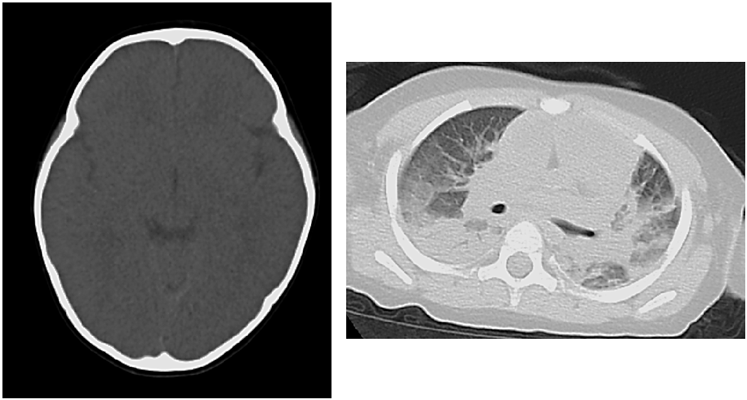

A blood acylcarnitine analysis was normal. This ruled out an organic acid or fatty acid metabolic abnormality. Computed tomography findings revealed cerebral edema, pulmonary edema and atelectasis, which indicated postmortem changes (Fig. 2). Nine hours after death, a pathologic examination revealed pulmonary edema, alveolar hemorrhage, and non-suppurative pericarditis with lymphocyte invasion into the epicardium. There was mild neutrophil infiltration into the myocardium, but no findings of myocardial necrosis or edema. There were no pathological findings of virus-induced changes, fulminant myocarditis, myocyte disarray, or myocardial hypertrophy (Fig. 3). We did not perform an electron microscopic study.

Fig. 2 Postmortem computed tomography scan